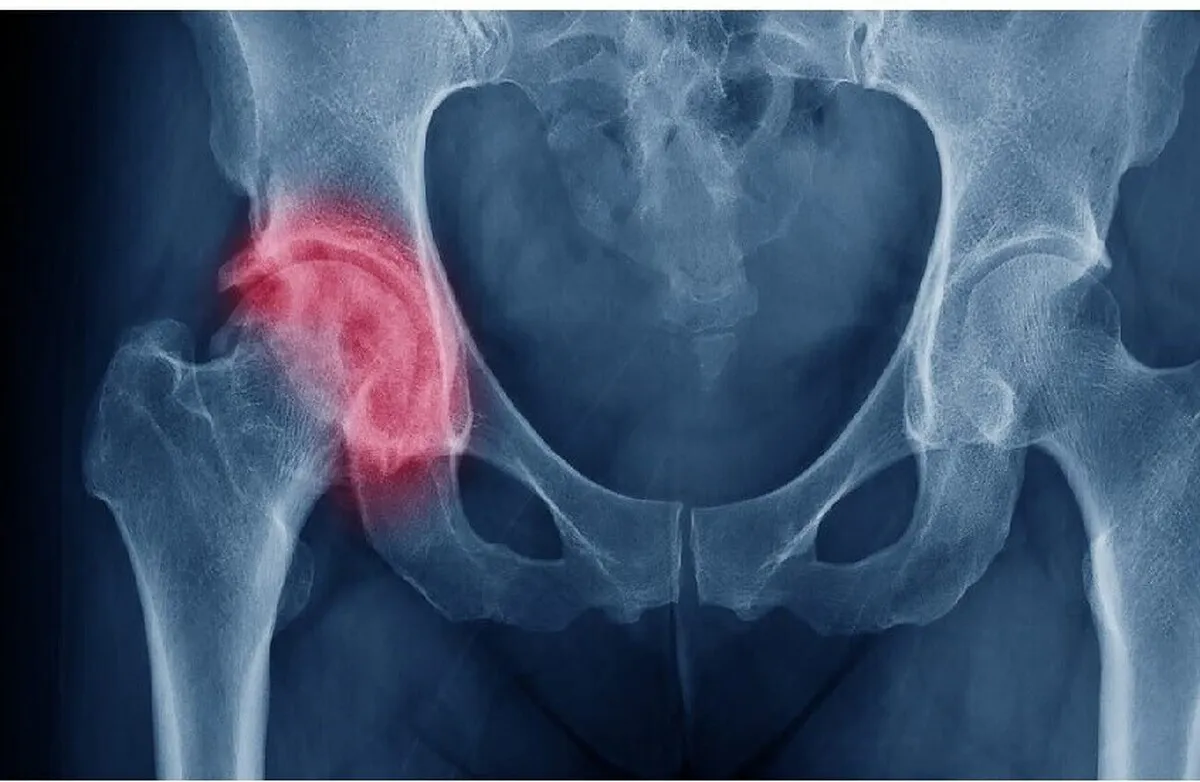

أعلنت شركة "روستيخ" الحكومية أن خبراء المعهد المركزي لجراحة العظام والكسور التابع للشركة ابتكروا منظومة داخلية لعلاج المفاصل التالفة.

أفادت وکالة آنا الإخباریة، ووفقا لمدير عام المركز فيكتور سبيكتور تجرى في روسيا حوالي 170 ألف عملية جراحية لاستبدال مفصل الركبة والورك سنويا. منها 10-15 بالمئة عمليات جراحية ثانوية لاستبدال الأطراف الصناعية.

بعد رحيل الشركات الأجنبية المنتجة للأجهزة الطبية، بما فيها المخصصة لاستبدال المفاصل، أصبحت مهمتنا الأساسية هي إنتاج معدات ومواد محلية. وقد أصبحت المنظومة الداخلية التي ابتكرت في المركز أولها وهي مصممة لاستبدال الأطراف الصناعية التي استخدمت لأكثر من 15 عاما. ويقدر الخبراء الطلب على هذا المنتج خلال السنوات العشر المقبلة بأكثر من 135 ألف وحدة.

وقد أجرى الجراحون الروس أول عملية ناجحة استغرقت ثلاث ساعات، لتركيب مفصل ورك صناعي واستعادة بناء عظم الفخذ والحق (تجويف صغير في عظم الورك) باستخدام الابتكار الروسي.

وتتكون المنظومة الداخلية المبتكرة من طرف اصطناعي مصنوع من التيتانيوم وعناصر إضافية للتعويض عن عيوب العظام، ما يضمن التثبيت الموثوق والتكامل مع النسيج العظمي.